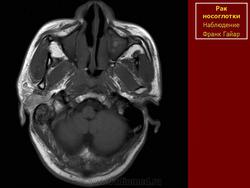

ЛОР. Онк. Рак носоглотки. +

Рак носоглотки